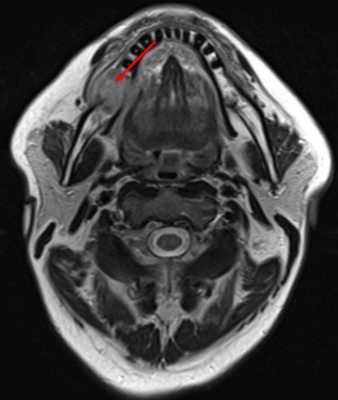

(Слева) На рисунке показано наиболее частое расположение ПКР дна полости рта: в пределах 2 см от средней линии в передних отделах. При анализе изображений важно оценить распространение опухоли каудально с инвазией подбородочно-язычной и челюстно-подъязычной мышц, кзади по направлению к корню языка, и кпереди или латерально с инвазией нижней челюсти. С этой целью может потребоваться и МРТ, и КТ. Другой целью методов визуализации является оценка вторичного поражения лимфатических узлов.

(Справа) При МРТ Т1ВИ в сагиттальной проекции визуализируется объемное образование с сигналом низкой интенсивности по сравнению с мышцами языка, прилежащее вплотную к нижней челюсти по средней линии.

(Слева) При МРТ Т1ВИ С + FS в аксиальной проекции у этого же пациента не четко визуализируется объемное образование передних отделов дна полости рта, прорастающее в правую подъязычную железу. Обратите внимание на отсутствие кортикальной пластинки с гипоинтенсивным сигналом в прилежащих отделах нижней челюсти, что подтверждается и при КТ в костном окне. Патологически измененные лимфоузлы не определяются.

(Справа) На фото этого же пациента, полученном при клиническом обследовании, также видна опухоль в передних отделах дна полости рта. Фото позволяет оценить локализацию опухоли и подъязычных желез. На операции была подтверждена опухоль T4aN0 с инвазией нижней челюсти.